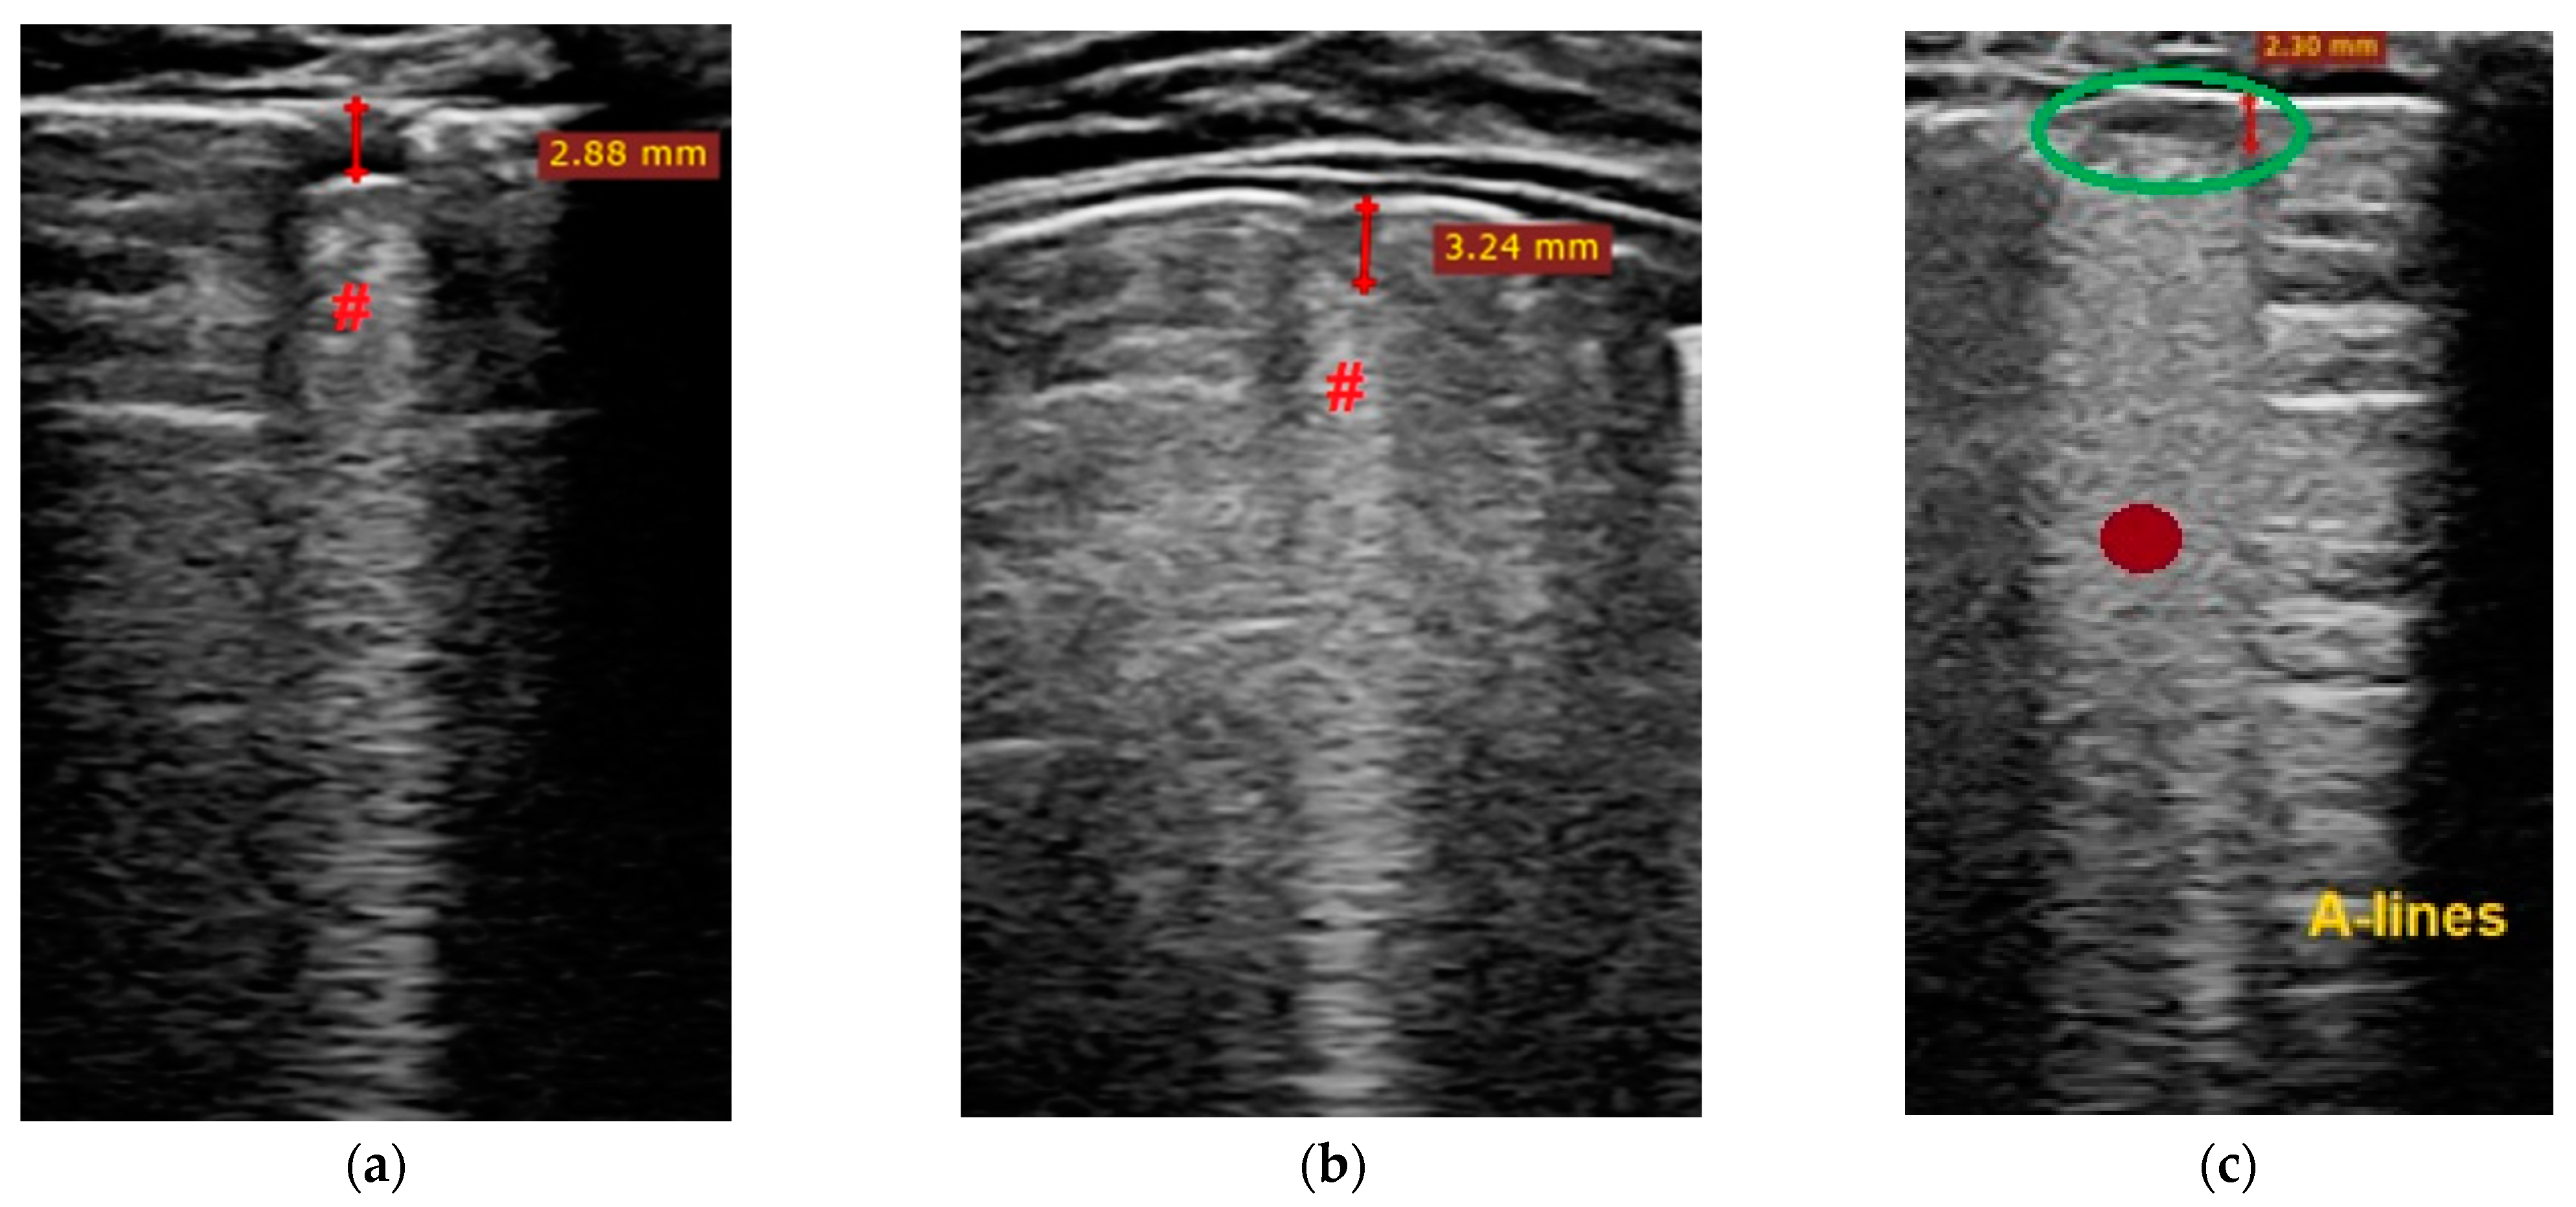

- Transverse physiologic A-lines that depict healthy parenchyma;

- Isolated/sparse vertical B-lines are equivalent to interstitial edema;

- Confluent vertical B-lines correspond to alveolar edema;

- Subpleural/peripheral consolidations;

| LUSS = 0 Points | LUSS = 1 Point | LUSS = 2 Points | LUSS = 3 Points |

|---|---|---|---|

| Normal/physiological A-lines | More than 2 B-lines (sparse B-lines) with associated pleural abnormalities | Coalescent or confluent B-lines | Large peripheral consolidation (wider than 1 cm) in association or not with air bronchogram |

| One or two B-lines per intercostal space | ‘White-lung’ aspect or small peripheral consolidation (smaller than 1 cm) |